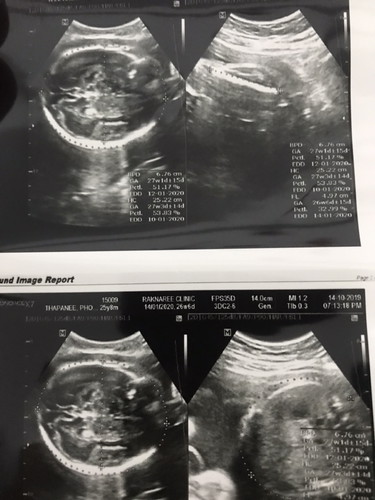

26สัปดาห์แล้วจ้า หมอบอกว่าเพศหญิง ดูตรงไหนอ่า ดูไม่ออกจ้า ^^??

ในภาพนี้น่าจะเป็น หัวกะโหลกน้อง กับช่วงลำตัวน้องรึป่าวค่ะ แม่ บ้านนี้ ตอนซาวด์ดูเพศ หมอจับภาพให้ ชัดเจนมาก เด็กผู้ชาย 😊

ภาพนี้เป็นการขนาดกะโหลกศรีษะเด็กค่ะแม่ บอกไม่ได้เลยว่าเพศอะไร แต่เชื่อหมอไว้ก่อนจ้า

ภาพซาร์แม่ น่าจะเป็นหัวน้องนะแม่ ไม่มีตรงไหนที่บอกเพศในภาพ ต้องลองถามหมอดูนะคะ

26วีคเท่ากันเลยค่ะ รูปนี้ตอน14วีค ผช. แม่คลอดวันไหนคะ เรานัดผ่า 16มค.63นี้ค่ะ